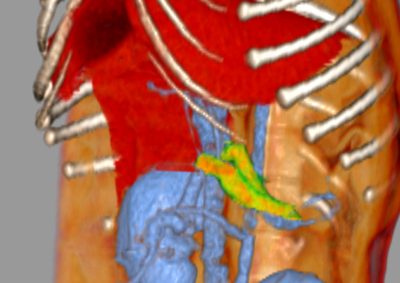

軟部組織外科 注意 ボタンをクリックした先に、治療中および手術中の画像が説明で使用されている場合がございます。 そのような画像に弱い方は閲覧なさらないようお願いいたします。 軟部組織外科腫瘍外科 ジャックラッセルテリアの胃腫瘍 救急・集中治療軟部組織外科 呼吸困難を起こした唾液瘤 軟部組織外科救急・集中治療呼… 喉頭麻痺 軟部組織外科 胆嚢粘液嚢腫 軟部組織外科救急・集中治療 胃捻転拡張症候群 GDV 軟部組織外科腫瘍外科 大腸腺癌 軟部組織外科腫瘍外科 肺葉切除術 軟部組織外科腫瘍外科 唾液腺癌 Salivary gland carcinoma 軟部組織外科救急・集中治療 鼠径ヘルニア嵌頓による腸閉塞 軟部組織外科腫瘍外科 胃部分切除術・ビルロートI 軟部組織外科 門脈シャント 軟部組織外科内科 猫の会陰尿道瘻設置術 <«89101112131415> 症例カテゴリー 放射線治療整形外科軟部組織外科脳神経外科内科腫瘍外科救急・集中治療リハビリテーション科腫瘍内科内視鏡科脳神経科呼吸器外科中医・漢方猫の腎移植循環器科